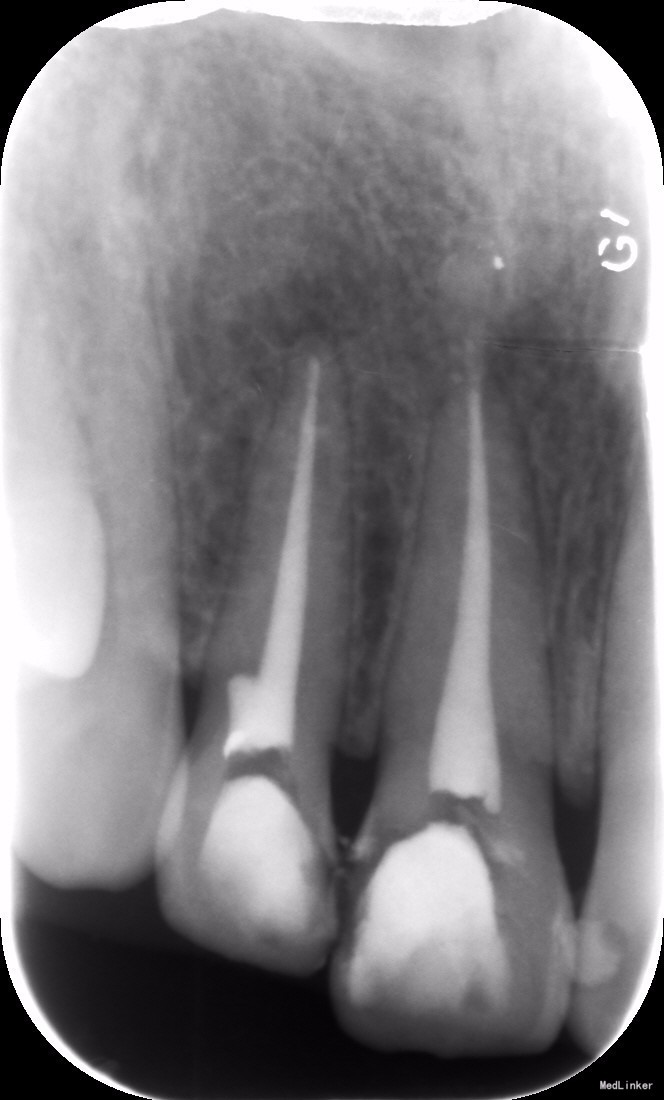

检查: #11,#12牙体变色,色暗,未见明显牙体缺损、龋坏,#11 #12 叩(+-),松(-),冷热测及电测无反应,牙龈未见明显异常。 X线示:#11#12根尖周未见明显阴影

诊断:#11#12牙髓坏死 治疗: 治疗前跟患者进行沟通,让患者充分了解治疗的费用及过程,患者表示知情同意。 #11#12碧兰麻下开髓、揭全顶,拔髓,次氯酸钠和双氧水交替超声冲洗,测量工作长度,根管预备,封Ca(OH)糊剂2两周,ZOE暂封。 两周后复诊检查,患牙无叩痛,暂封存。去暂封,次氯酸钠和双氧水交替超声冲洗,再次测量工作长度,干燥,热牙胶充填。树脂充填治疗。